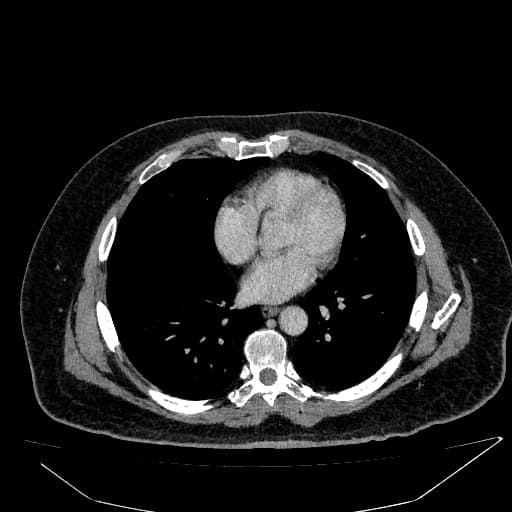

Gan có tăng âm lan tỏa, kèm bóng cản phía sau làm cản trở đánh giá nhu mô gan sâu và cơ hoành. Bờ gan vẫn trơn, không dấu hiệu hình thái của xơ gan (cirrhosis).

Vùng nhu mô gan không bị thoái hóa mỡ (fatty sparing) khu trú liền kề hố túi mật (gallbladder fossa).

Gan biểu hiện tăng âm lan tỏa kèm bóng cản phía sau, làm hạn chế đánh giá nhu mô gan sâu và cơ hoành, phù hợp với thoái hóa mỡ gan nặng (severe hepatic steatosis – độ III).

Thoái hóa mỡ gan lan tỏa - độ III (diffuse hepatic steatosis - grade III)